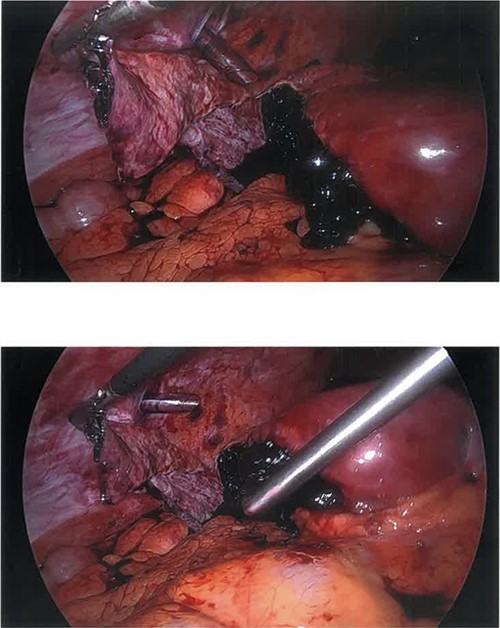

Diagnostic laparoscopy revealed a large ruptured, segment six, liver cyst with ~500 ml of blood suctioned from the abdomen. The majority of the liver cyst was exophytic. A harmonic (ultrasound energy device) was used to perform a partial hepatectomy (deroofing). The majority of the cyst wall was removed leaving minimal cyst wall at the liver bed (Fig. 3). Histopathology report detailed fragments of benign simple cyst wall and blood clot, without any evidence of malignancy. The patient had no post-operative complications and was sent home on post-operative day two. She was seen at her 2-week and 3-month post-operative clinic follow up. She had an uneventful recovery from her operation.

Ruptured hemorrhagic hepatic cyst wall and remaining hemorrhagic component mid-suctioning.